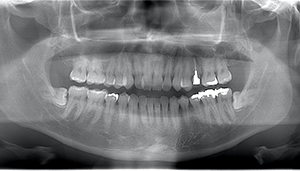

左下親知らずがたまに痛み、

できれば痛くなく抜きたい症例

- 抜歯前写真(レントゲン)

- 抜歯前写真(CT画像)

| 抜歯内容 | 左下親知らずが横向きになって半分埋まっている状態だったため、麻酔を行い、親知らずの奥の歯ぐきに切開をいれ、歯が囲んでいる骨を削り、歯の頭の部分を削って出し、その後根の部分に器具をかけて抜歯しました。 親知らずが一部神経に近い部分があったため、術後に麻痺が出る可能性がありました。このケースでは事前にCTを撮影し、歯の位置、根の方向、神経との距離を確認していたため、幸い麻痺が出ることはありませんでした。 術後1週間経過して糸取りをして治療は終了となりました。抜歯後3日間は腫れと痛みで大変だったが、糸取りをする頃には痛みも腫れも無くなったと患者さまも喜んでおられました。 |